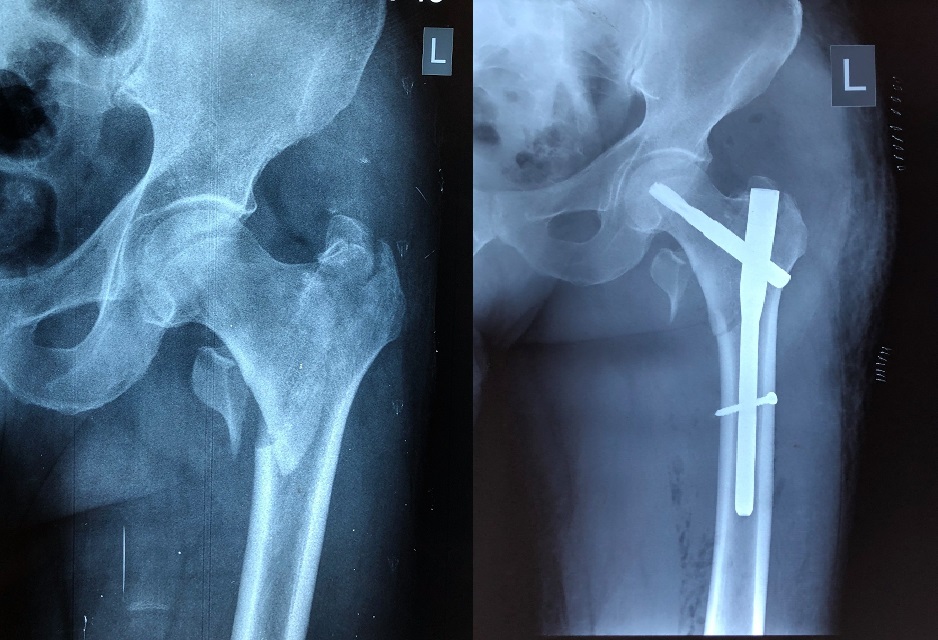

وقال الطبيب المعالج بالمستشفى، الدكتور احسان محمد فرج، في حديث صحفي، أن فريق طبي برئاستنا نجح بعملية تثبيت عظام الفخذ لمريض يبلغ من العمر (72) عام من خلال تقنية الشيش المقفل.

وبين فرج، أن المريض يعاني من هشاشة في العظام ونتيجة لشدة خارجية ادى الى حدوث كسر في أعلى عظم الفخذ الايسر وأن هذا النوع يعد من الكسور الشائعة لدى كبار السن.

موضحاً، أن مستشفى الكفيل اوجدت الحل لمعالجة هكذا حالات من خلال توفيرها لفرق طبية متخصصة وفرق تمريضية متميزة، مضيفاً الى توفير احدث الاجهزة والمستلزمات الطبية ومن ضمنها تقنية شيش العظم المقفل (PFNA)